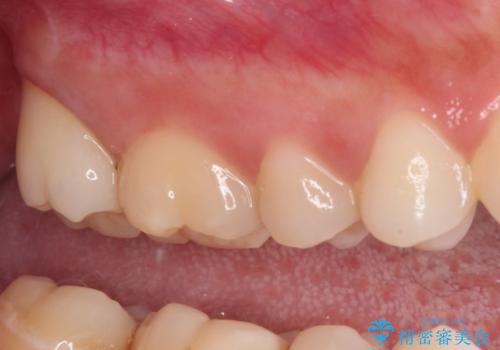

親知らずの抜歯により歯を覆っていた歯肉が切除され、不快感の原因のひとつでもあった歯周ポケットが改善され、奥歯を気にせずに生活できるようになりました。